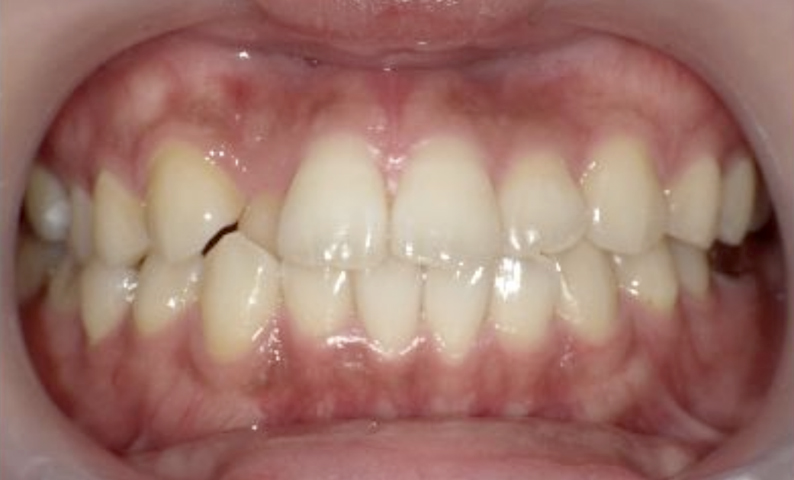

症例_024 上下顎の部分矯正

治療期間:13ヶ月金額:51万円+税女性前歯のガタガタ八重歯

| Before | After |

|---|---|

|